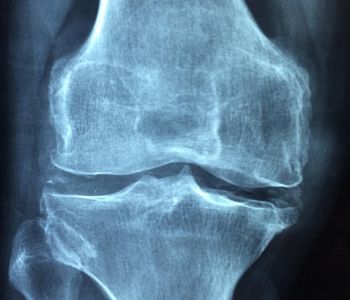

Een gewrichtsontsteking of artritis is een ontstekingsreactie van het gewricht. Vaak ontstaat er bij een ontsteking extra vocht in het gewricht, waardoor het normale functioneren belemmerd wordt. Andere tekenen van een ontsteking zijn zwelling, roodheid en warmte.

Heel passend voor mij! Ben naar dokter geweest (eindelijk!). Heb foto's laten/moeten nemen van (pijnlijke ) knie. Heb bericht gekregen dat 'knie versleten is'. Bij verder gebruik gaat dit ergere gevolgen hebben voor heupen...kromme benen, zegt dokter. Zou bij operatie ('nieuwe halve knie') soelaas vinden. Zegt dr.

Weet niet wat ik er moet van denken. Op Mynexuxhealth staan wel de foto's, maar ik kan niet aan 't verslag. Dat verslag is wel op scherm pc van de dr maar krijg niet de kans dit helemaal te lezen/of te bekijken. Ik denk dat dr. denkt dat ik er toch niks van begrijp. Soms (als ik langer op de benen sta/ga knik ik door die knie, en da's pijnlijk. Daarna kan ik moeilijk gaan tot na langere rust... dan 'gaat' het weer. Op dit moment spuit dr. een - zoals hij het noemt - siliconen in de knie. Grote twijfels bij mij, over operatie en behandeling.

Heb zelf knie ontstekingen gehad. Dokter heeft scan laten doen. Uitslag: versleten gewricht!